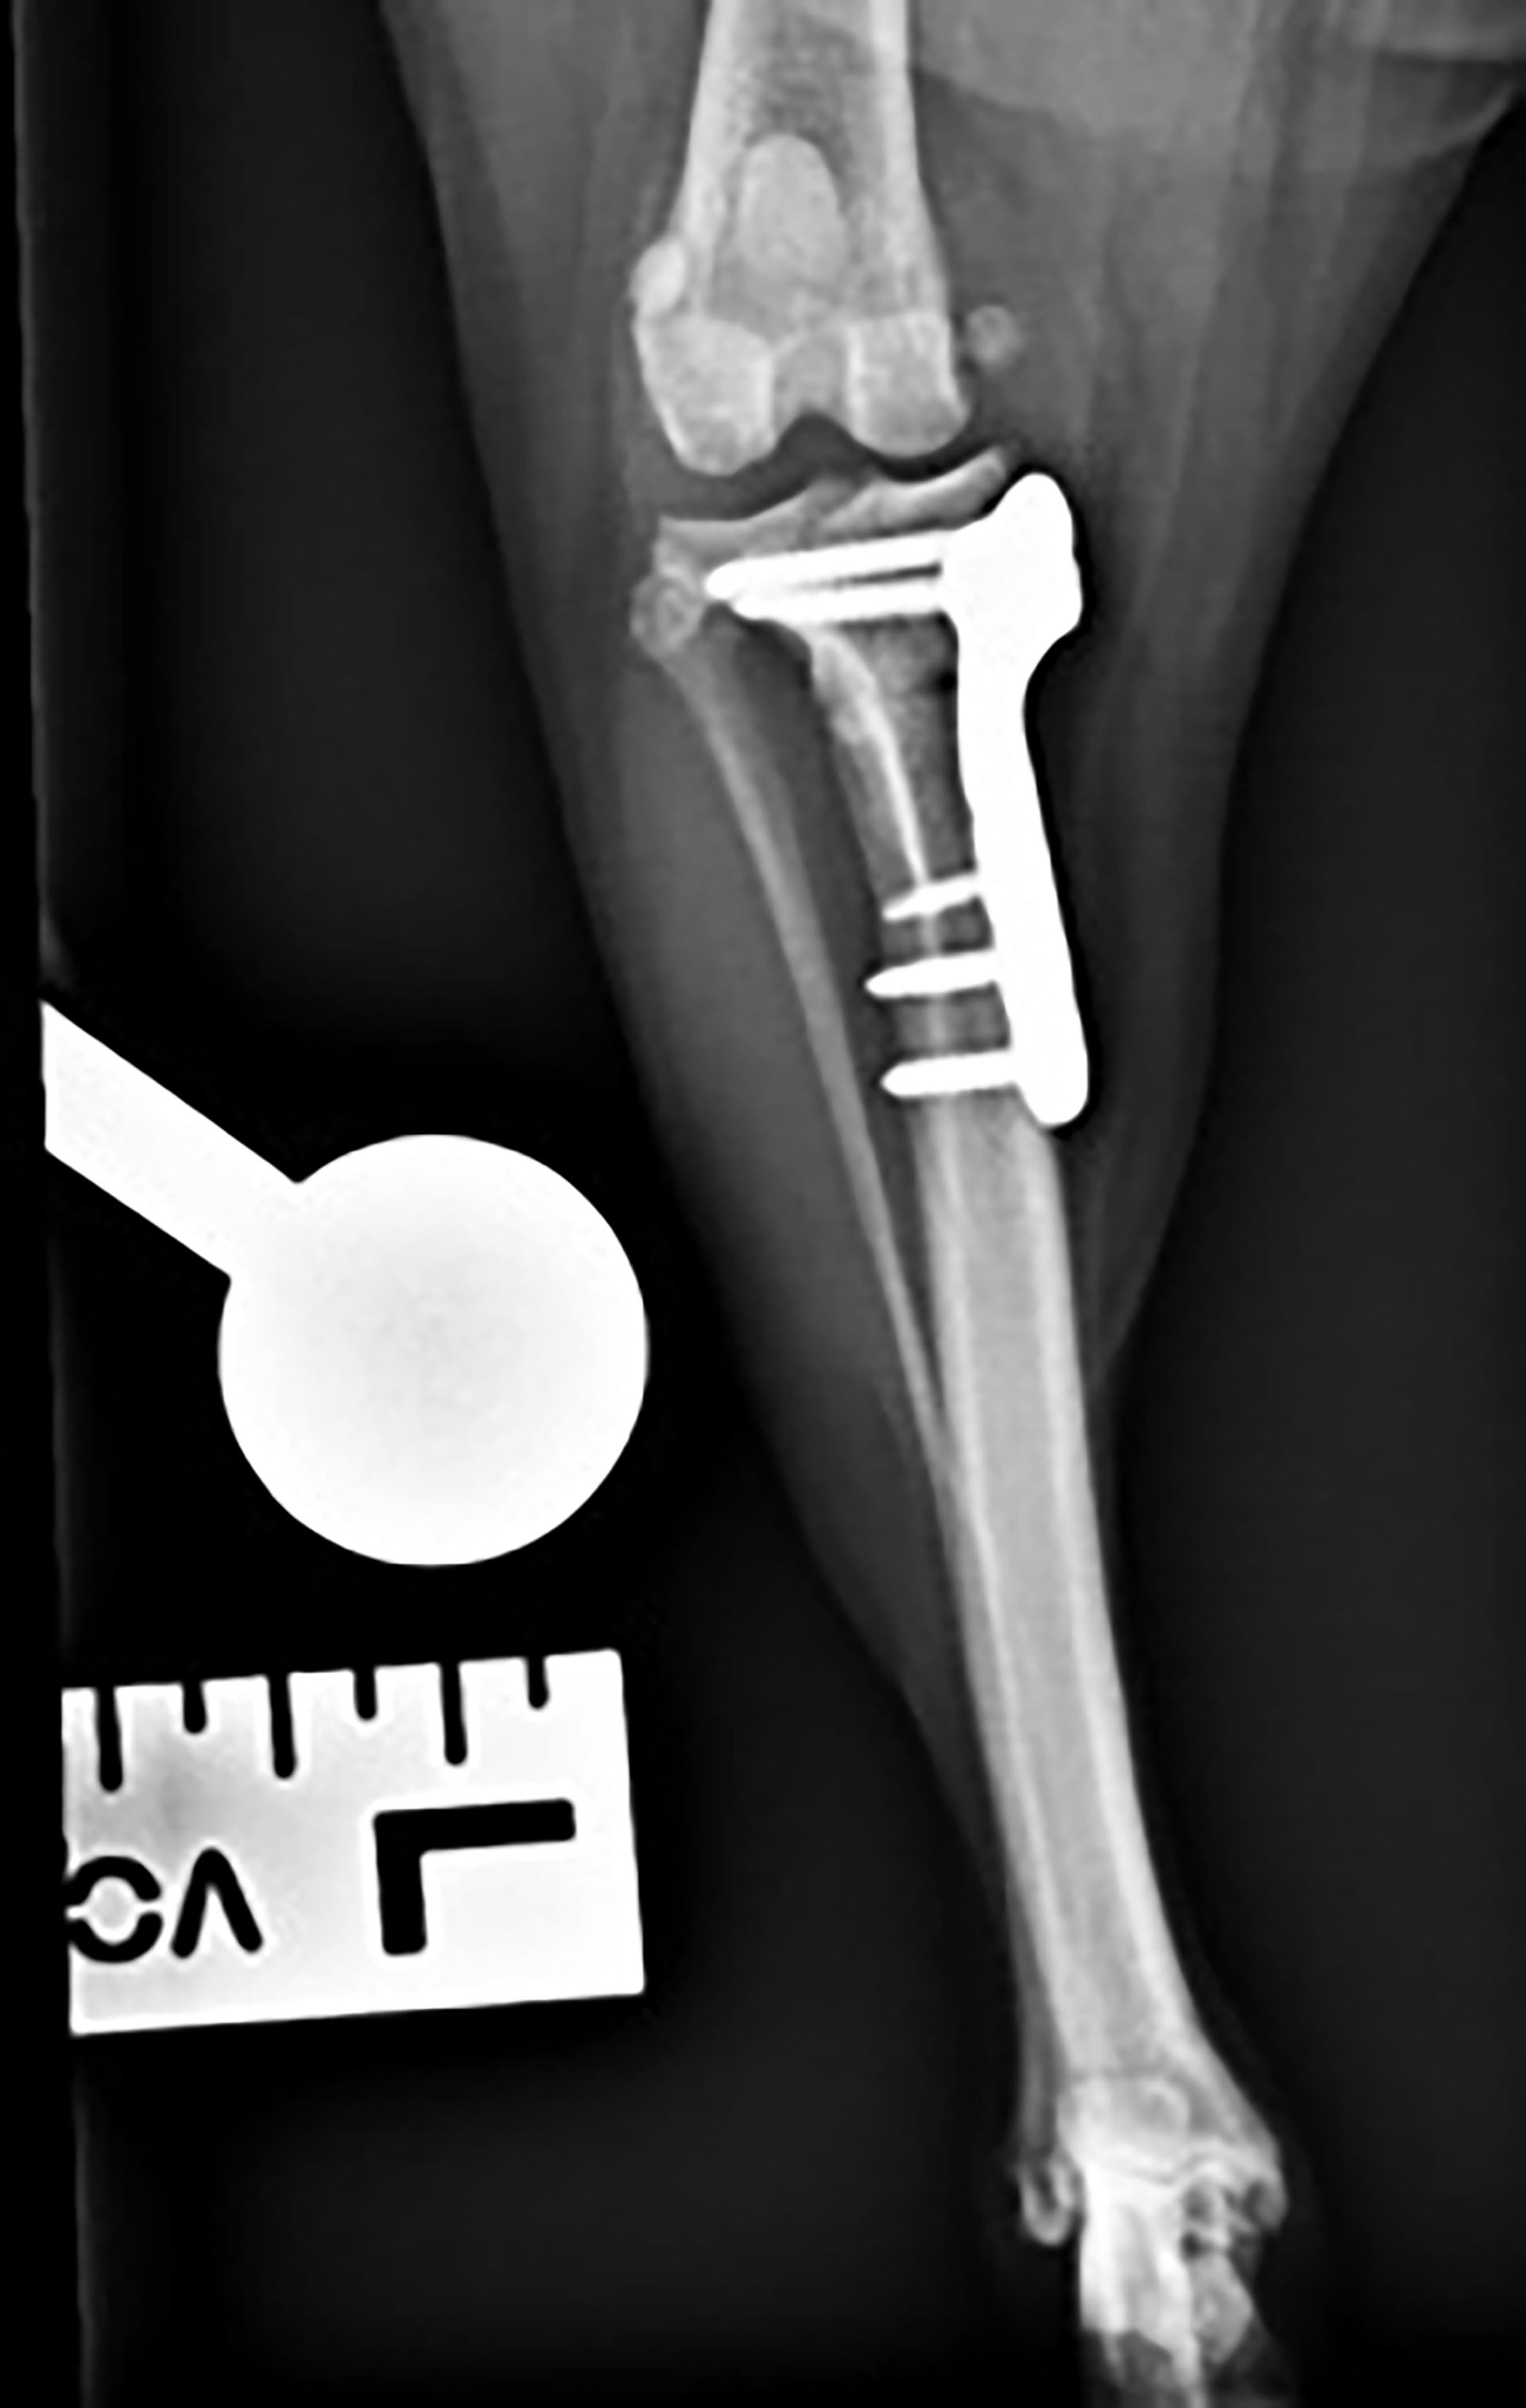

Røntgenkontrollen skulle egentlig bli utført seks uker etter operasjonen, men hadde blitt utsatt grunnet sykdom hos eier. Hunden var i god allmenn form og hadde også hatt det veldig fint ukene før kontrolltimen. Hun hadde fått 1 mg/kg robenakoksib per os en gang daglig. Matlyst og drikkelyst var som det pleide å være. Hunden hadde jevn og fin respirasjon. Auskultasjon av hjertet ble utført og hun hadde jevne, rytmiske hjerteslag med en samsvarende puls. BCS ble estimert til 6/9, vekten var stabil. Slimhinnene var rosa og fuktige med en kapillærfylningstid på ett sekund. Temperaturen var 38,4 ˚C. Hunden trådde fint på begge bakben og viste ingen tegn til halthet. Hun ble sedert med 5 µg/kg dexmedetomidin og 0,1 mg/kg butorfanol intramuskulært for røntgenkontroll (Figur 8 og 9).

Figur 8. Laterolateral projeksjon av venstre kneledd.

Figur 9. Kraniokaudal projeksjon av venstre kneledd. Platen sitter godt med skruer (pil).

Vurdering av røntgenbilder: Bilder som var tilgjengelig for vurdering var laterolateral projeksjon og kraniokaudal projeksjon. Kvaliteten av bildene var tilstrekkelig. Platen satt godt og skruene var korrekt plassert slik som de var postoperativt. Det var tegn på god heling av osteotomien med mild kallusdannelse.

Plan videre for denne hunden var å øke turlengdene med 20 til 30 minutter uken etter, deretter øke turene med fem minutter per uke i bånd. Hunden kunne gå løs om seks til åtte uker. Medisiner ble seponert. Vi anså dette som en vellykket operasjon, og hunden var smertefri.